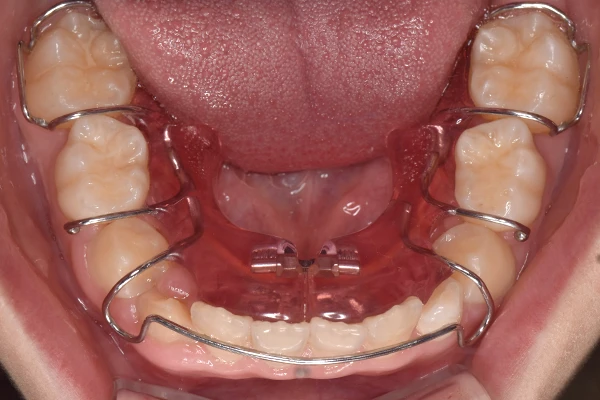

反対咬合

| 診断名・主訴 | 前歯反対咬合 |

|---|---|

| 年齢・性別 | 12歳・男性 |

| 治療期間・回数 | 1年半 18回 |

| 治療に用いた主な装置 | リンガルアーチ(前方誘導弾線) |

| 抜歯部位 | なし |

| 治療費 | 35万円(税抜) |

| リスク・副作用 | 装置による違和感・疼痛・歯肉退縮・歯根吸収・虫歯のリスクなど |

治療前

治療中

治療後